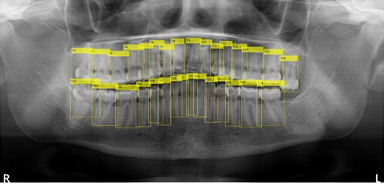

歯牙の全自動認識法

従来、歯科医院ではパノラマレントゲンの撮影後、歯科医師が目視で患者の歯牙情報をカルテや患者管理ソフトに入力し、診査・診断等を行っていました。本システムは、パノラマレントゲンの画像データから歯牙情報の有無をAI技術で自動解析し、また解析後の歯牙情報をアウトプットするものです。

本技術(特許出願中 出願番号:特願2020-132917)は、Springer Nature社のScientific Reportsに2020年11月6日付けで掲載された論文「Optimization Technique Combined with Deep Learning Method for Teeth Recognition in Dental Panoramic Radiographs」に基づきます。